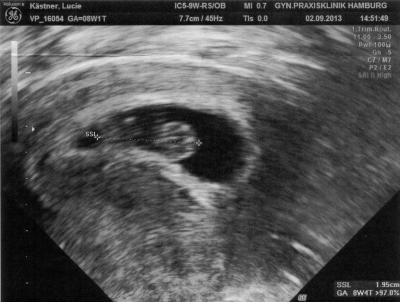

Alles supi, Baby geht's prima. Wo wir letzte Woche noch leicht hinterher gehinkt haben, haben wir jetzt sowas von aufgeholt.

Bild zu Feedback zum Arzttermin - Forum für April - Mamis